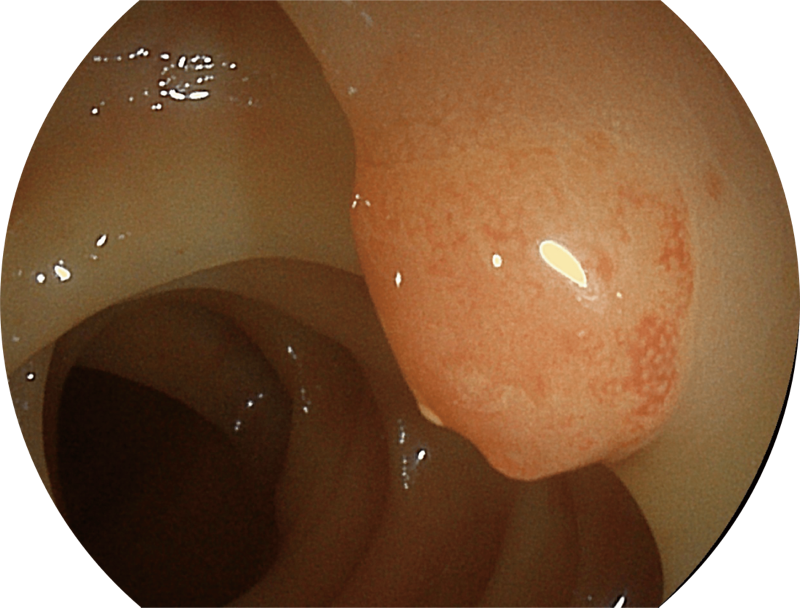

百万级像素高清传感器,1080P全高清视频信号输出,图像清晰。

能够凸显黏膜浅层血管轮廓和黏膜表面微结构,适用于中、近景观察下的早癌精确诊断。